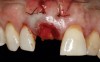

(17.) Implant placed 1-mm distal to the midline of the edentulous space, corresponding with the planned location of the gingival zenith. Note the lack of sufficient bone buccal to the implant that necessitated further grafting.

Figure 17

Prior to the initiation of the surgery, the surgical guide was tried in to confirm proper seating and stability (Figure 15). A flapless approach was not considered because the need for further bone grafting at the time of implant placement had been anticipated through the digital planning. A slightly palatal crestal incision was made, followed by two vertical incisions on the mesial and distal aspects of the edentulous site in order to preserve the papilla and avoid additional esthetic compromise to the anterior sextant. Next, a full-thickness flap was elevated to facilitate removal of the tenting screw and permit visualization of the buccal plate (Figure 16). A standard guided protocol was followed to place the implant, and its final position mirrored that of the digital plan. As predicted, the prosthetically driven implant position resulted in an insufficient buccal plate (Figure 17); therefore, additional guided bone regeneration was performed to reinforce the area and prevent future breakdown (Figure 18 and Figure 19). Making periosteal incisions could have compromised the blood supply to the flap, so instead, it was stretched in order to achieve tension free coronal advancement.31The flap was secured utilizing horizontal mattress sutures with additional supportive interrupted sutures to ensure primary closure (Figure 20). An immediate postoperative periapical radiograph (Figure 21) and CBCT scan (Figure 22) were taken, demonstrating a final implant position centered with the planned location of the gingival zenith.

The digital wax up allowed the implant position to be planned based on the ideal prosthetic position of the final restoration (Figure 14). The planned implant position adhered to the aforementioned guidelines for ideal implant placement regarding the buccal, interproximal, and apical bone, and its platform would be located 4-mm apical to the planned restorative margin. In the coronal plane, the implant was centered with the gingival zenith in a position that was located approximately 1-mm distal to the midline of the edentulous space. Following implant planning, a tooth-supported surgical guide was designed and then 3D-printed to facilitate fully guided surgical implant placement.